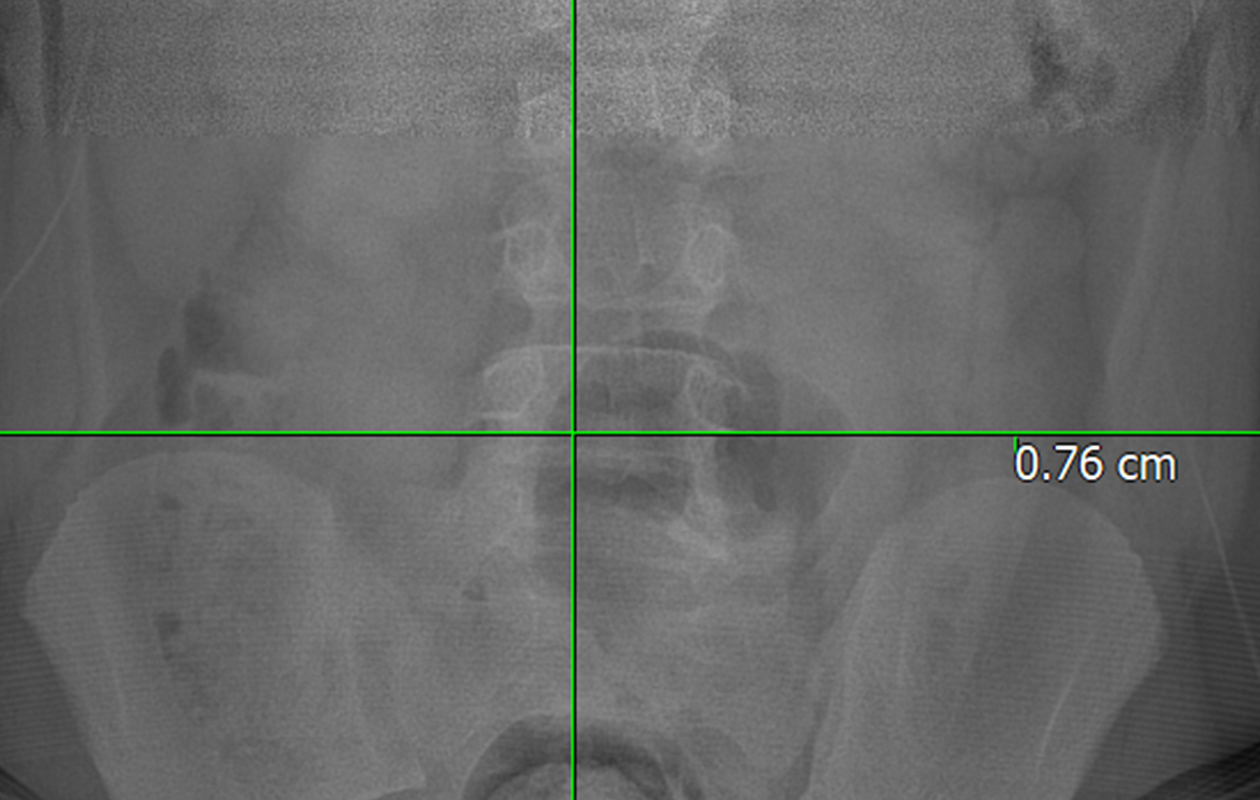

척추 측만증 진단은 어떻게 이루어지나요?

- 신체 검진과 X-ray 촬영

- 아담스 전방 굴곡 검사

- X-ray로 Cobb's angle(만곡 각도) 측정